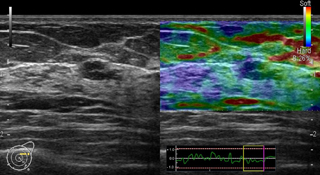

乳腺が発達している若い世代でも、しこりが見つけやすく、小さなしこりも発見できるのが特徴です(検査画像サンプルその1・2)。一方、乳がんの石灰化を画像に映し出すことは難しく、がんが見落とされる心配があります。

当院の超音波診断装置では、乳腺組織の硬さまでわかるようになっており、触診の代わりに画像で確かめることができるようになってきています。放射線被ばくがないため、妊娠中の女性でも検査を受けることが可能です。痛みを伴わず、身体的苦痛がないのもメリットです。